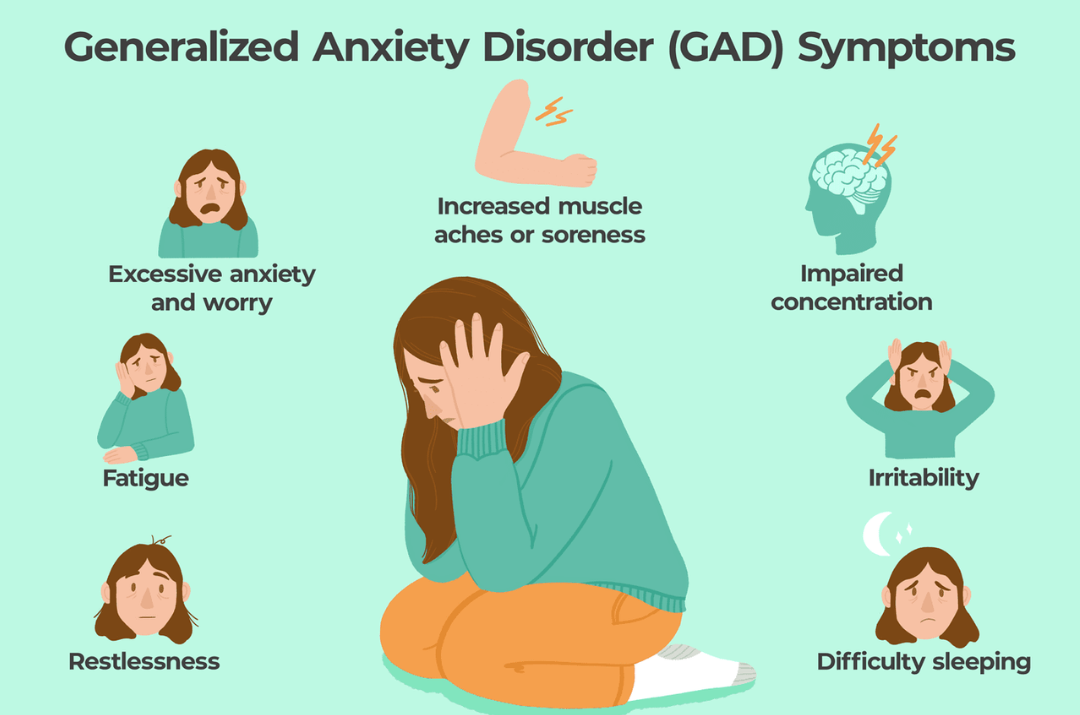

Disorders refer to abnormal conditions affecting physical or mental health, disrupting normal functioning. They can range from physical ailments like heart disease to psychological issues like anxiety. These conditions may be caused by genetics, environment, or lifestyle. Diagnosis often involves medical exams and tests. Treatment can include therapy, medication, or lifestyle changes to improve quality of life.

Disorders refer to abnormal conditions affecting physical or mental health, disrupting normal functioning. They can range from physical ailments like heart disease to psychological issues like anxiety. These conditions may be caused by genetics, environment, or lifestyle. Diagnosis often involves medical exams and tests. Treatment can include therapy, medication, or lifestyle changes to improve quality of life.